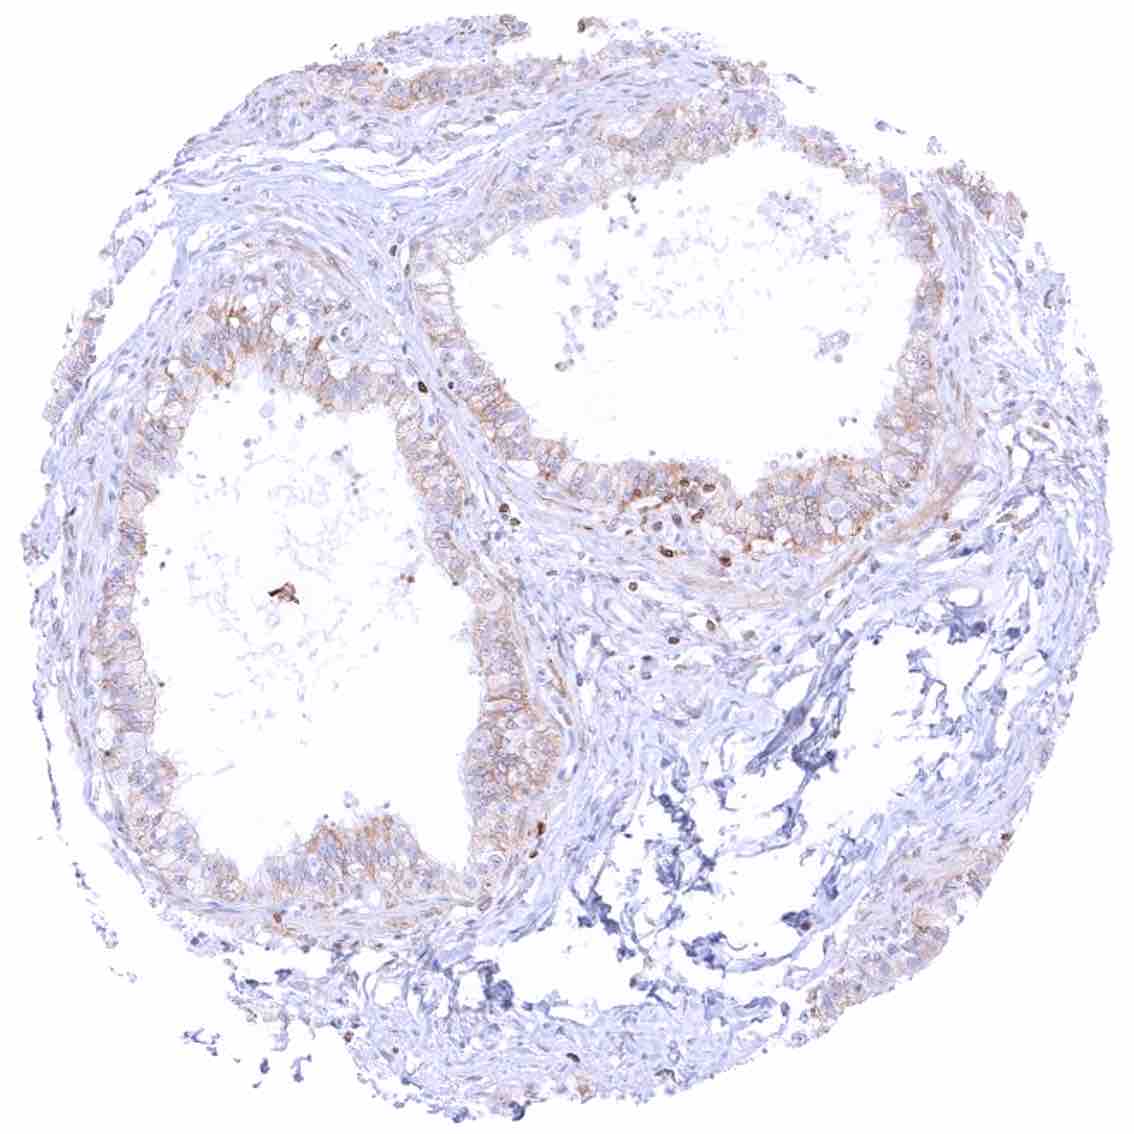

Prostate – Weak to moderate bcl-2 staining of a fraction of basal cells.